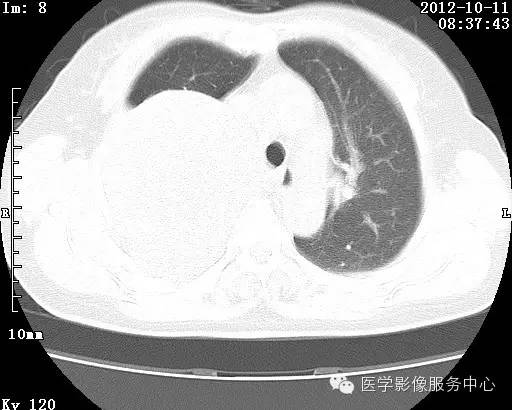

病史:女 65岁咳嗽咳痰 右肺巨大肿块就诊。

错构瘤的主要组织成分包括软骨、脂肪、平滑肌、腺体、上皮细胞,有时还有骨组织或钙化。错构瘤一般为实质致密的球形、卵圆形,也可以是分叶状或结节状,大多数直径在3cm以下。

错构瘤的发病年龄多数在40岁以上,男性多于女性。 绝大多数错构瘤(约80%以上)生长在肺的周边部,紧贴于肺的脏层胸膜之下,有时突出于肺表面。其特征钙化为爆米花样钙化,内有脂肪软骨成分等等。最常见的部位是胸膜下肺实质内,其次为主支气管或肺叶、肺段支气管内。

瘤内出现“爆米花样钙化”是诊断的主要指标之一。早期的点状、斑片状及结节状钙化 随时间增加钙化数量及范围会增加,最终可能演变 为爆米花样钙化;

另一项主要指标是瘤测得脂肪成分是诊断错构瘤。